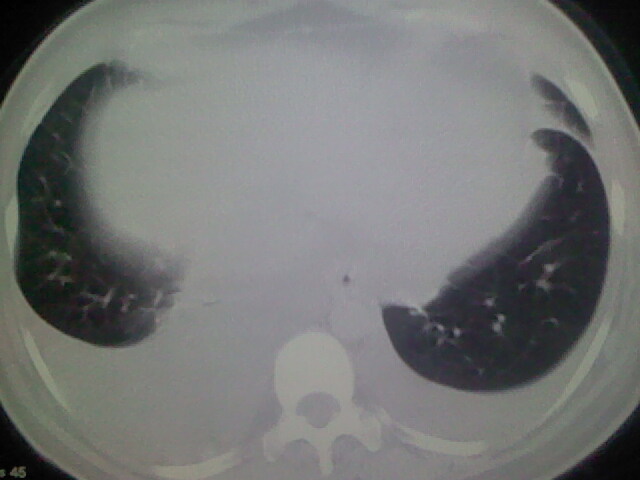

女,24,剖腹产后,突觉胸痛,干咳,不能平卧

临床资料及影象表现支持围产期扩张型心肌病改变,心衰。

肺水肿,双侧胸腔积液,心影增大.考虑妊娠心脏病

考虑产后心肌病,心功能不全,肺水肿,双侧胸腔积液。

考虑产后心肌病,心功能不全,肺水肿,双侧胸腔积液。不排除羊水栓塞可能。